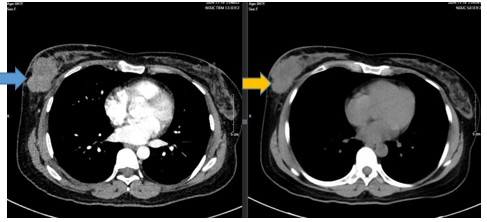

- CT ngực trước điều trị:

Hình 2: Vú phải vị trí 1/2 dưới có khối tổn thương ~50x34mm, thâm nhiễm xung quanh, xâm lấn gây dày da vú lân cận. Hố nách trái có vài hạch đường kính ngắn 9mm, vỏ dày 7mm, ngấm thuốc mạnh sau tiêm.

- CT ngực trước và sau điều trị tân bổ trợ

Hình 4: Vú phải vị trí 1/2 dưới , có khối ~50x34mm (Trước điều trị mũi tên xanh). Sau điều trị giảm còn ~ 24x17 mm (Sau điều trị mũi tên vàng)